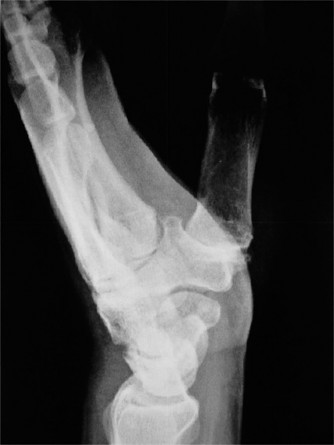

CASE 40 A 16-year-old male baseball player presents to your office for evaluati…